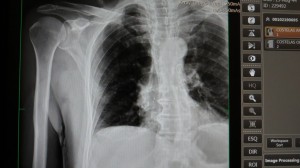

O Hospital Santo Antônio iniciou o atendimento com o aparelho de Raios-X com digitalizador de imagem, um equipamento no qual é possível produzir imagens em tempo real com até milhares de tons cinza, possibilitando mais nitidez e um diagnóstico ainda mais preciso.

Foi necessário realizar adequações na sala de procedimentos para instalações do aparelho. O equipamento de Raio-X de alta frequência para aplicação em radiodiagnóstico, permite examinar todas as regiões anatômicas tanto para traumatologia quanto para ortopedia. O Conjunto Radiológico é composto pelos seguintes módulos individuais: mesa, estativa, mural Bucky, painel digital, gerador e transformador.